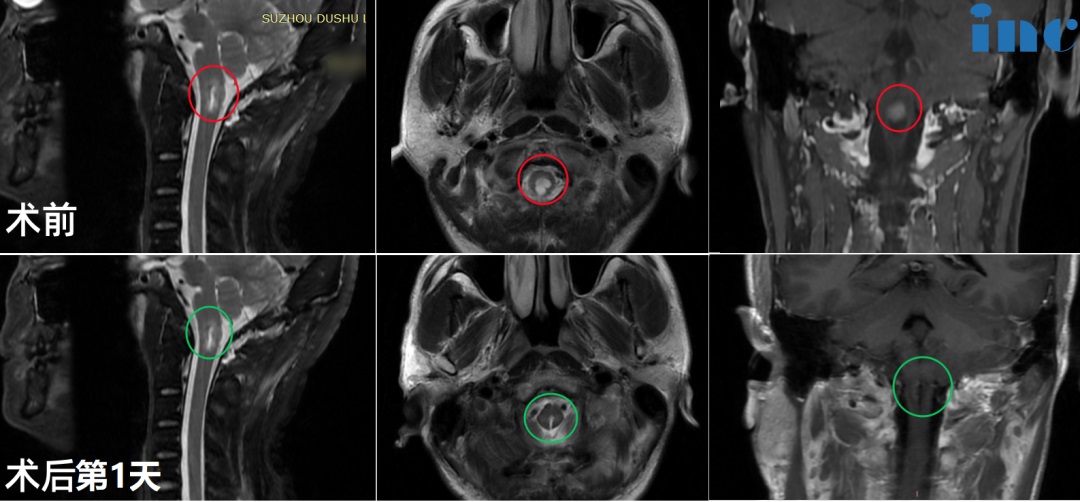

1、19岁男孩-延髓海绵状血管瘤

◉手术时间:2022年11月巴教授疑难示范手术期间

◉患者情况:2022 年 9 月 8 日19岁的阿朔出现无明显诱因的头痛和晕胀感,从颞侧到枕后。10 月 10 日于苏州独墅湖医院行颅脑核磁提示延髓异常信号,考虑海绵状血管瘤。

◉治疗过程:在2022中德学术交流-INC巴特朗菲教授示范国际疑难脑瘤手术直播,INC旗下的国际神经外科教授德国巴特朗菲教授受邀围绕“脑干海绵状血管瘤的手术”做课程演讲,并进行线上线下延髓手术示范直播。手术顺利全切阿朔延髓海绵状血管瘤,直播观看人次达7000多,除了神经外科医生观看外,还有即将接受教授手术的患者家属共同观看。

◉术后情况:术后1天巴教授ICU查房,阿朔意识清楚、对答如流、四肢活动灵活;术后5天,可正常站立、行走;术后8天,阿朔状态很好,正逐步回归正常生活。术后一个月,阿朔回到大学校园,回归正常的学习和生活。术后3个月,阿朔还接受了INC专访,交流自己的治疗经历,希望能够帮到更多的人。